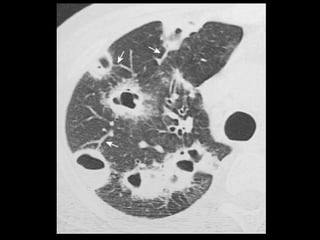

Êmbolo Séptico TC: modalidade importante para confirmar a presença de êmbolos sépticos quando a radiografia convencional de tórax permanece negativa; TC: nódulos bilaterais mais numerosos nas regiões periféricas dos pulmões e nas bases; Os nódulos podem ser bem circunscritos ou mal definidos e com frequência apresentam escavações; O sinal do vaso nutriz pode estar presente em 60- 70% dos casos.

• 48.